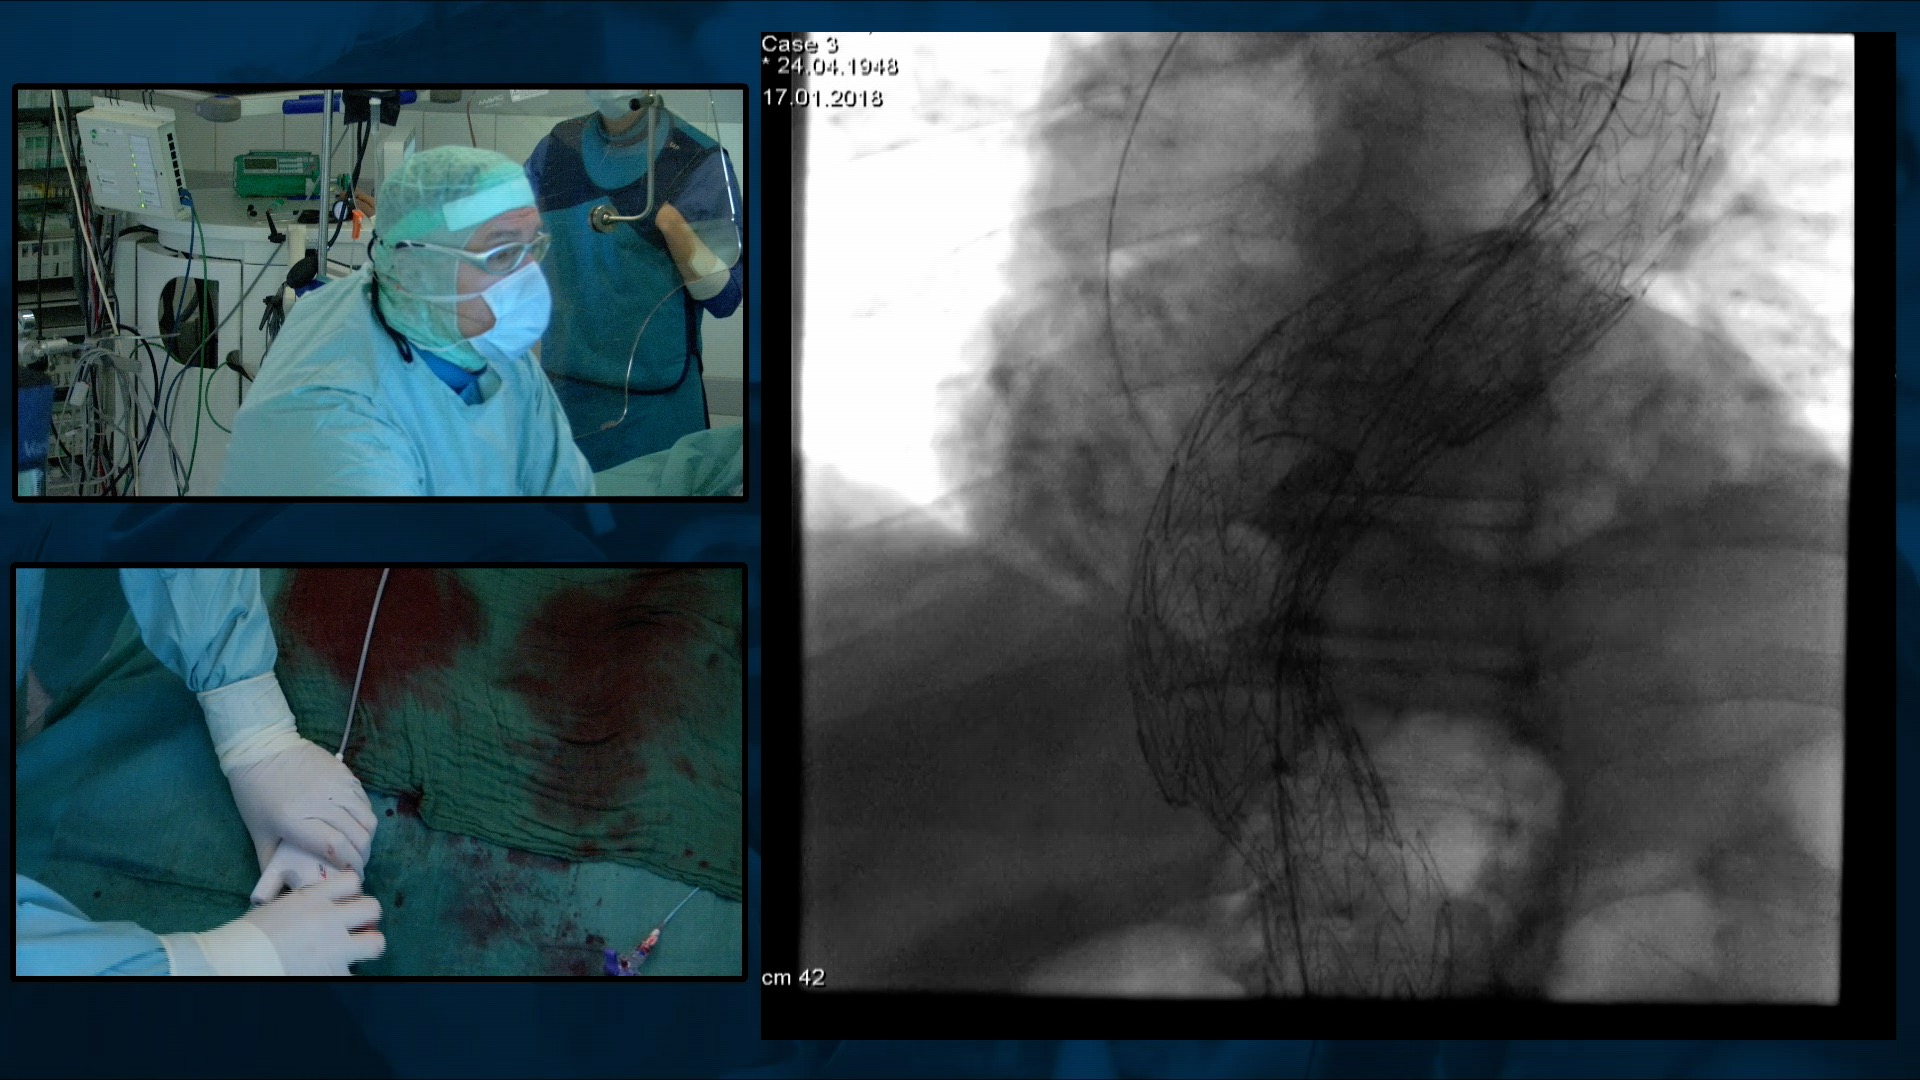

Complex PTCA: Experts' analysis